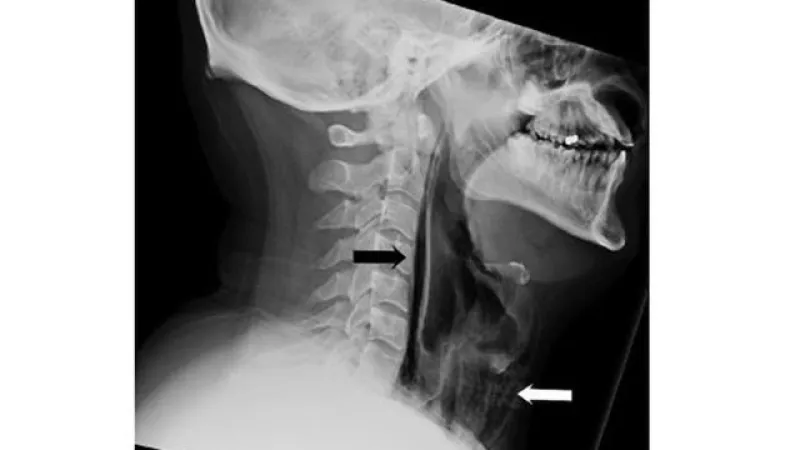

وأوضح الأطباء أن كتم العطاس قد تؤدي للوفاة نتيجة تضرر الأوعية الدموية الدماغية والإصابة بنزيف المخ أو حدوث تمزق في الحلق أو في طبلة الأذن او تسرب الهواء المضغوط من العطسة المكتومة ليصب الحجاب الحاجز بأضرار كارثية أو حدوث كسور أضلاع القفص الصدري خاصة مع كبار السن الناتج عن الاندفاع المفاجئ للهواء المضغوط إلى الرئتين بسرعة كبيرة.